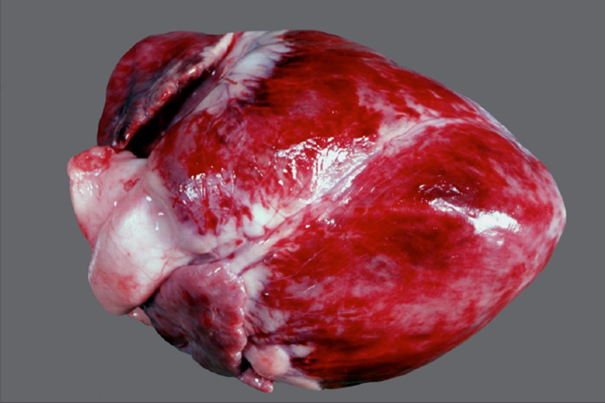

Mikrothrombose, Maulbeerherz

- flächenhafte Einblutungen in das Myokard

- angedeutet Hämatomartig

- häufig Selen/Vitamin E Mangel

- am unwahrscheinlichsten Trauma!